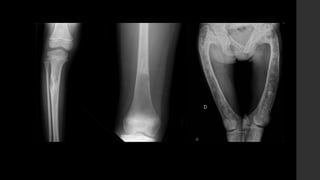

Fibroma no osificante.

• Lesión ósea no neoplásica más común.

• Son comunes en niños y adolescentes con un pico de incidencia entre los 10 y 15

años.

• Prevalencia 30 – 40% de todos los niños normales.

• Predominio M:F – 2:1.

• La mayoría son asintomáticas, pero las lesiones grandes (>3cm) pueden ser

dolorosas y pueden debilitar al hueso y predisponerlo a fracturas patológicas.

• Cuando son múltiples se asocian a Neurofibromatosis tipo 1, displasia fibrosa y

síndrome de Jaffe-Campanacci.

• RX y CT

 Típicamente son circunscritos, asimétricos, lesiones radiolúcidas corticales con un anillo esclerótico.

 Frecuentemente son multiloculadas.

 Se localizan en la metáfisis, adyacente a la fisis.

 Cuando el paciente crece, parece que migra lejos del núcleo de crecimiento.

 No hay reacción perióstica asociada.